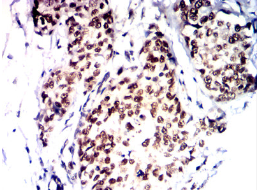

IHC    1/200-1/1000